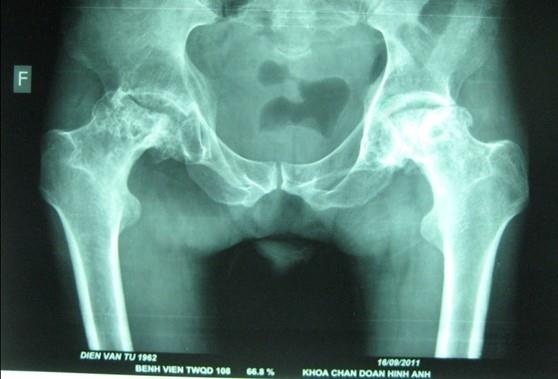

| Hình ảnh hoại tử vô khuẩn chỏm xương đùi hai bên giai đoạn muộn. |

Theo TS Việt, hoại tử vô khuẩn chỏm xương đùi là bệnh có tổn thương hoại tử tế bào và tuỷ xương do bị thiếu máu nuôi dưỡng. Vùng tổ chức hoại tử ban đầu tạo ra các vùng thưa xương, ổ khuyết xương, về sau dẫn tới gẫy xương dưới sụn, cuối cùng gây xẹp chỏm xương đùi, thoái hoá thứ phát và gây mất chức năng của khớp háng.

Đây là căn bệnh diễn biến âm thầm, từ từ, cho đến khi người bệnh cảm nhận được đau ở khớp háng, đồng nghĩa nó đã tiến triển đến giai đoạn trung bình trở lên.